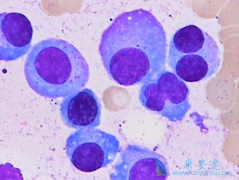

骨髓瘤是骨髓异常浆细胞增多并引起骨髓造血功能衰竭、使骨骼破坏而产生异常增多的单克隆免疫球蛋白为特征的浆细胞疾病。其发病率占据了血液系统疾病的10%至15%,发病率在恶性淋巴瘤之下。常见的临床症状主要包括为骨痛、贫血、高血钙、病理性骨折、压缩 ...

骨髓癌是浆细胞产生的恶性肿瘤,常侵犯多个部位骨髓瘤及组织。 骨髓癌 目前不能治愈,其治疗目标主要是维持生存。所以如何延长骨髓癌患者的寿命就成为了科研人员关注的重点。近期,一项研究表明,在标准的双药疗法中加入硼替佐米可以降低多发性骨髓癌患 ...

多发性骨髓瘤属于血液系统恶性肿瘤,所以如何对疾病进行精确的分期,如何获得更好的化疗疗效就显得非常重要。骨髓瘤细胞是高度分化的B淋巴细胞,增殖活性低,常规的细胞遗传学检查方法敏感性较差。使用常规细胞遗传学检查,可在30%~50%患者的骨髓瘤细胞 ...